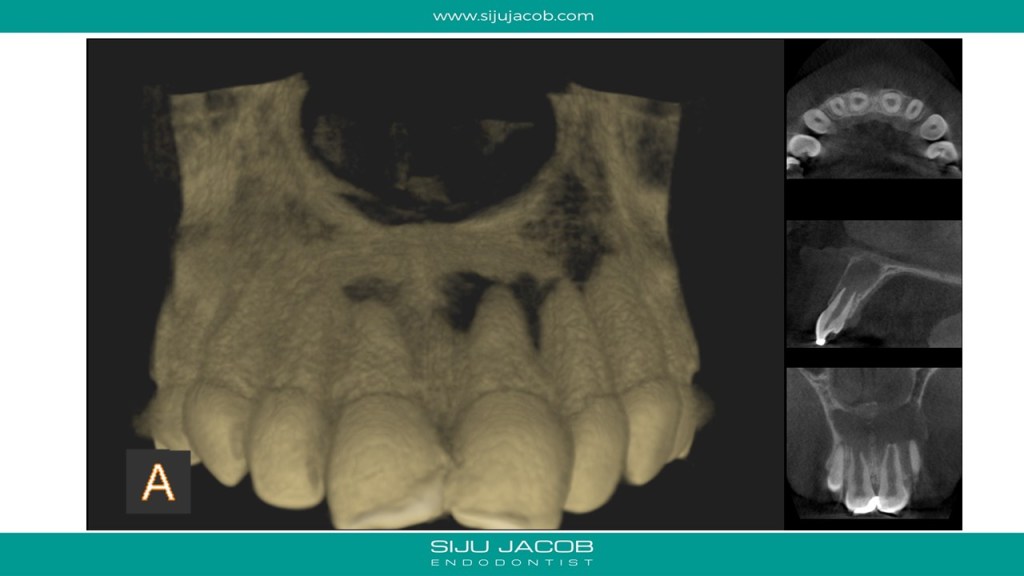

This was probably the largest lesion I ever treated. It had several interesting characteristics. It would be tough to explain with just pics. So, I made it into a short presentation